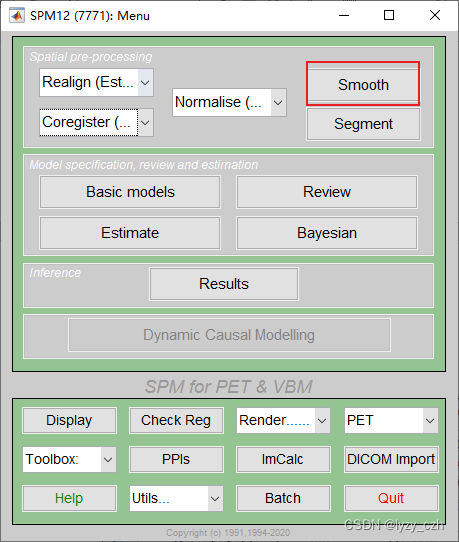

1) 打开matlab命令行输入spm pet,打开SMP12,界面如下

6)最后一步进行8mm的平滑

1、点击Batch